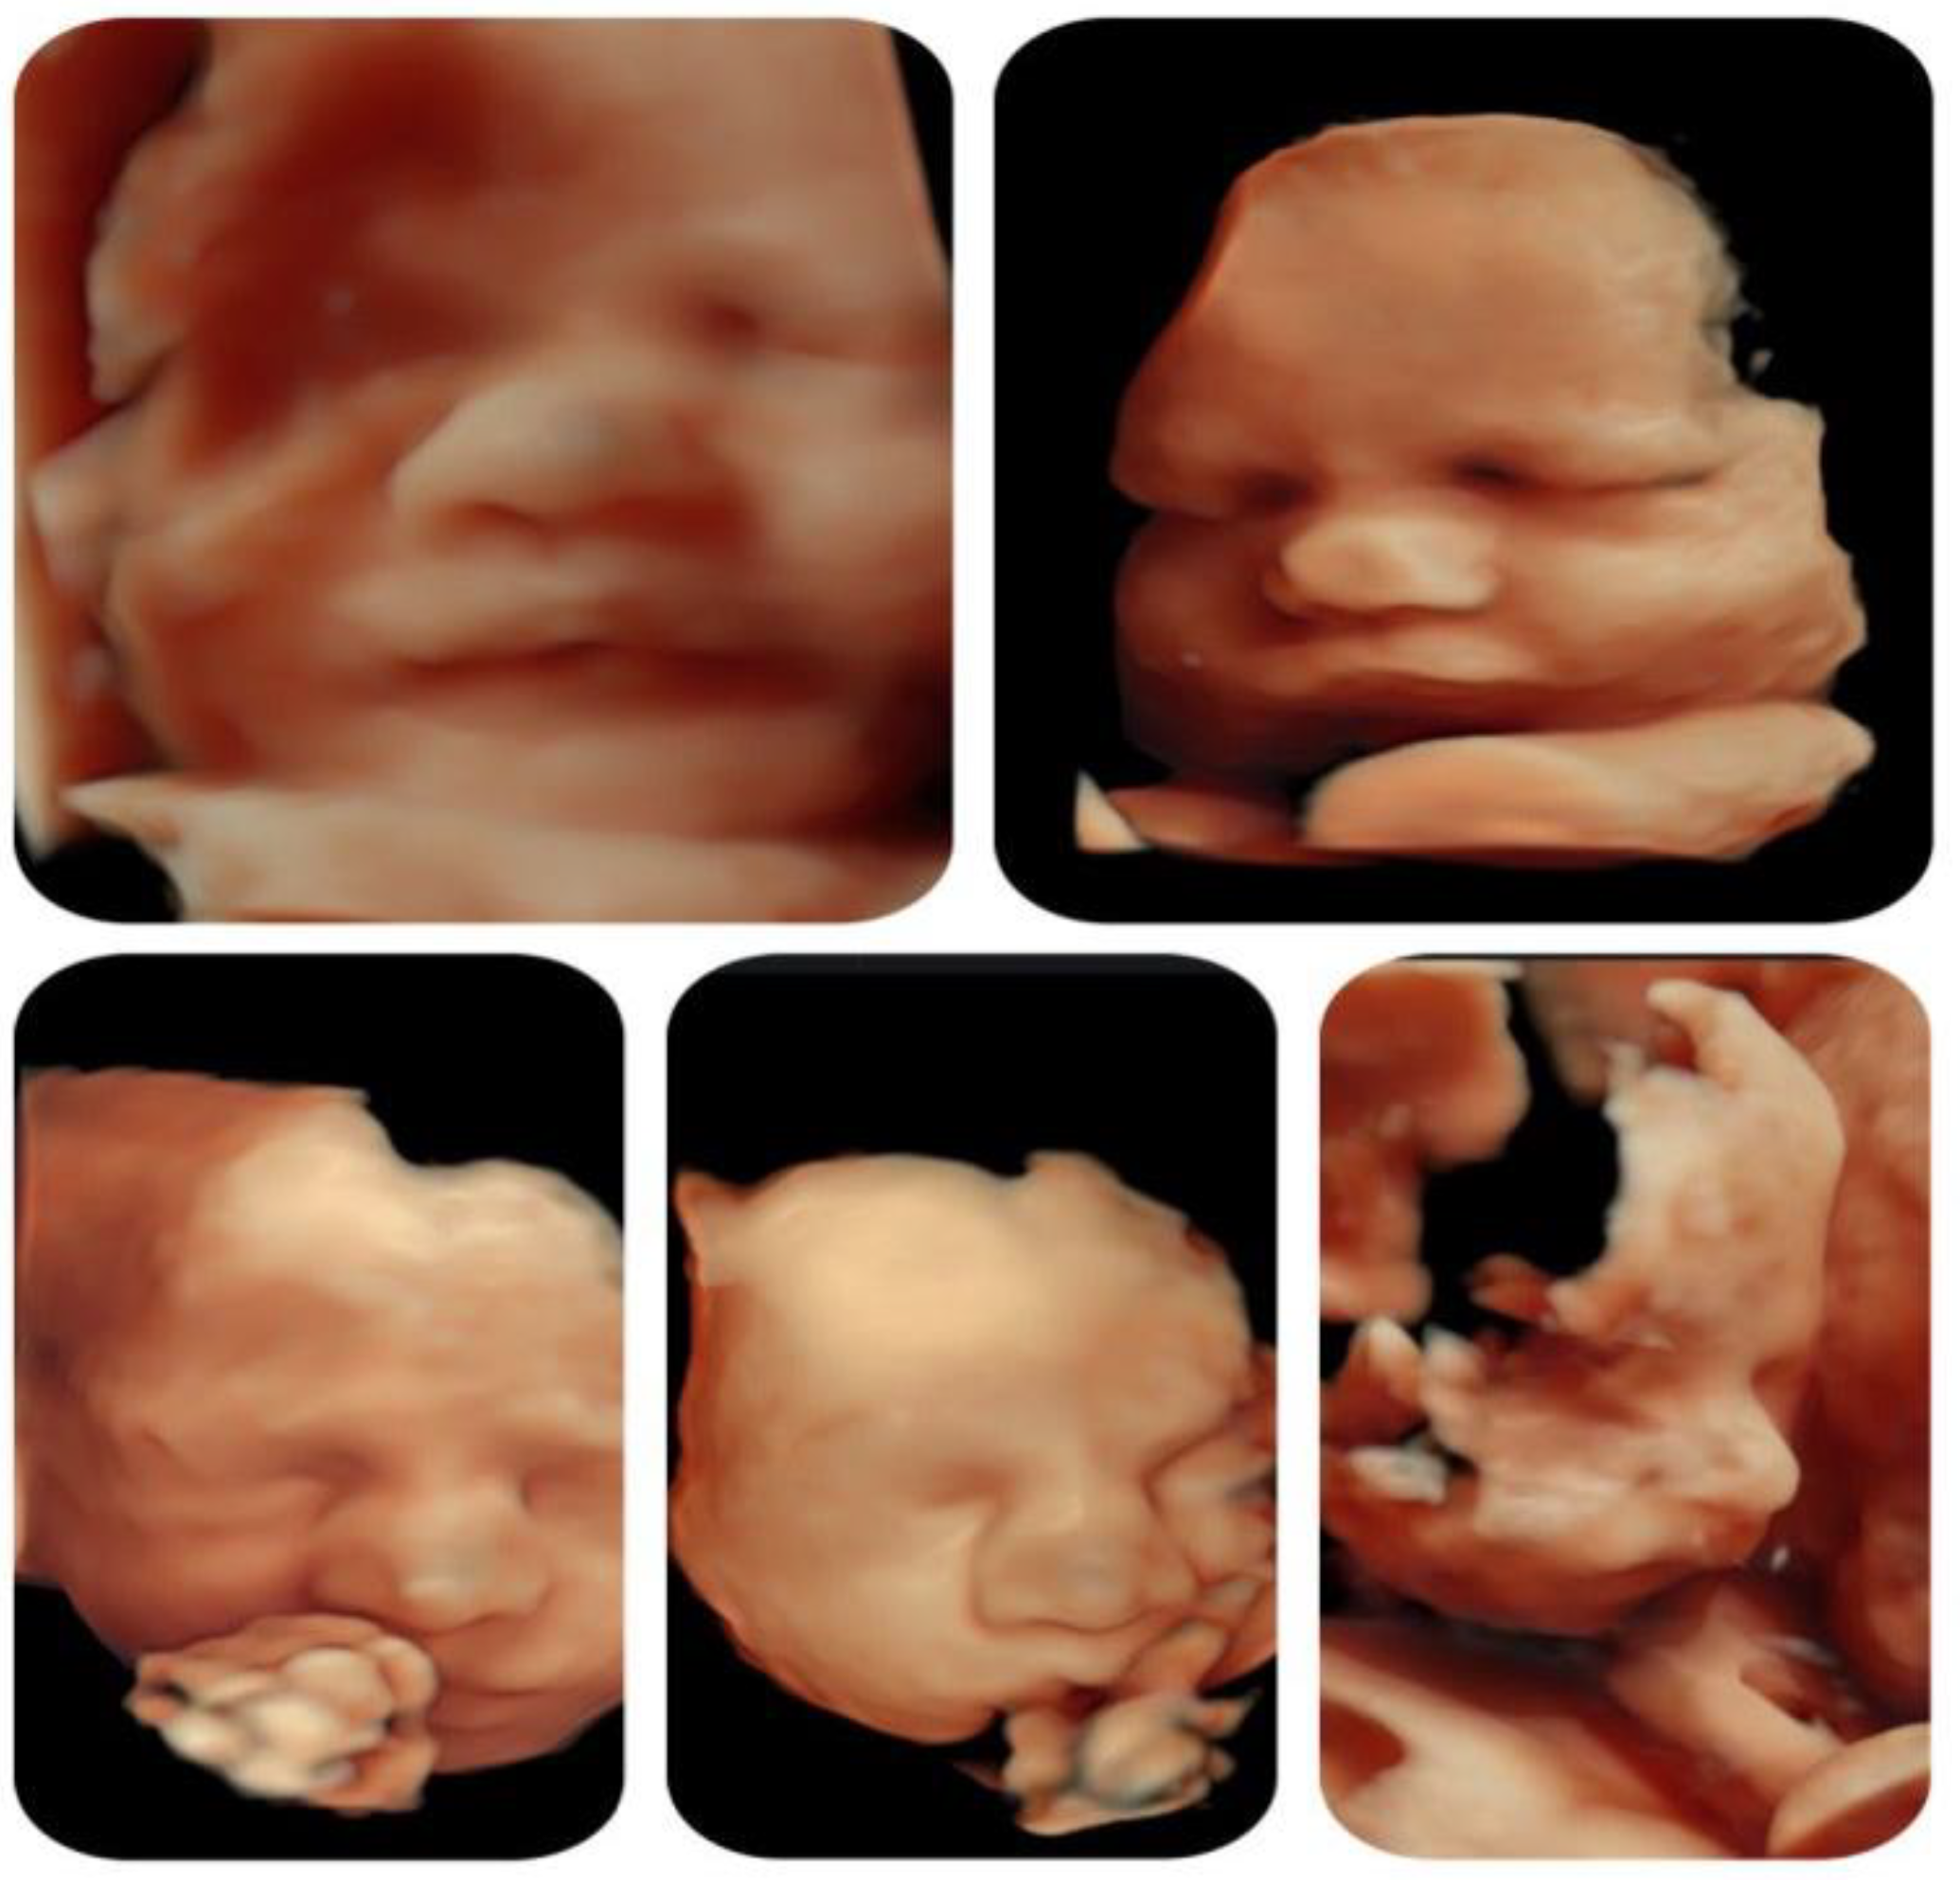

Other ultrasonographic findings | Polyhydramnios Enlarged CSP Thymus hypoplasia Bulbous nose |